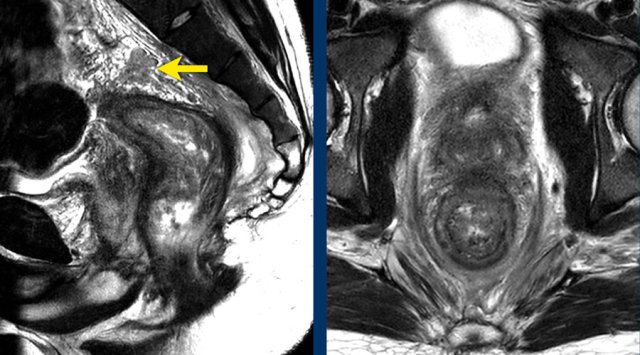

Images

The image on the left shows a tumor with a close relation to the peritoneum and the bladder (white arrow).

However there is no tumor extension beyond the muscularis propria anteriorly and the peritoneum is therefore not invaded.

The image on the right shows definite tumor invasion of the peritoneum (yellow arrow), i.e. a T4a tumor.